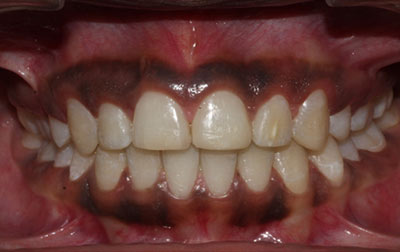

Painless Root Canal Treatment:

At Venkateshwar Hospital,Delhi, painless root canal treatment is performed with precision and care. Using advanced local anesthesia techniques, we ensure minimal discomfort during the procedure. The dentist gently removes the infected pulp, cleans the canal, and seals it with biocompatible materials. Our modern equipment and experienced practitioners ensure efficient and virtually pain-free treatment. Patients can resume normal activities shortly after the procedure, experiencing relief from the initial pain caused by the infection.

Laser Root Canal Treatment:

Laser root canal treatment is considered to be the future of dental care. Utilizing cutting-edge laser technology, weoffer a minimally invasive approach. Laser dentistry can be seamlessly integrated with traditional root canal techniques to enhance the efficacy of removing infected pulp and eradicating bacteria, thus preventing the likelihood of infection recurrence. The procedure often involves the utilization of a laser drill to gain access to the inner chamber, accompanied by a soft-tissue laser for thorough sterilization of the tooth's structures. This includes targeting intricate areas like the dentinal tubules, which may be challenging to treat using conventional methods. Laser root canal treatment provides a more precise means of exposing the tooth's pulp while conserving a greater portion of the healthy tooth structure. Additionally, the laser can be employed to reshape the dentinal walls of the canal if needed. Notably, this technique minimizes friction throughout the process, resulting in a significant reduction in discomfort and pain for the patient.